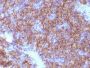

Chromogranin A is present in neuroendocrine cells throughout the body, including the neuroendocrine cells of the large and small intestine, adrenal medulla and pancreatic islets. It is an excellent marker for carcinoid tumors, pheochromocytomas, paragangliomas, and other neuroendocrine tumors. Co-expression of chromogranin A and neuron specific enolase (NSE) is common in neuroendocrine neoplasms. Reportedly, co-expression of certain keratins and chromogranin indicates neuroendocrine lineage. The presence of strong anti-chromogranin staining and absence of anti-keratin staining should raise the possibility of paraganglioma. The co-expression of chromogranin and NSE is typical of neuroendocrine neoplasms. Most pituitary adenomas and prolactinomas readily express chromogranin.Primary antibodies are available purified, or with a selection of fluorescent CF® Dyes and other labels. CF® Dyes offer exceptional brightness and photostability. Note: Conjugates of blue fluorescent dyes like CF®405S and CF®405M are not recommended for detecting low abundance targets, because blue dyes have lower fluorescence and can give higher non-specific background than other dye colors.

Positive Control

PC12 cells. Adrenal gland, bowel, thyroid, pancreas, or pheochromocytoma.

Neuroendocrine cells

Tumor expression

Neuroendocrine cancer|Pituitary cancer